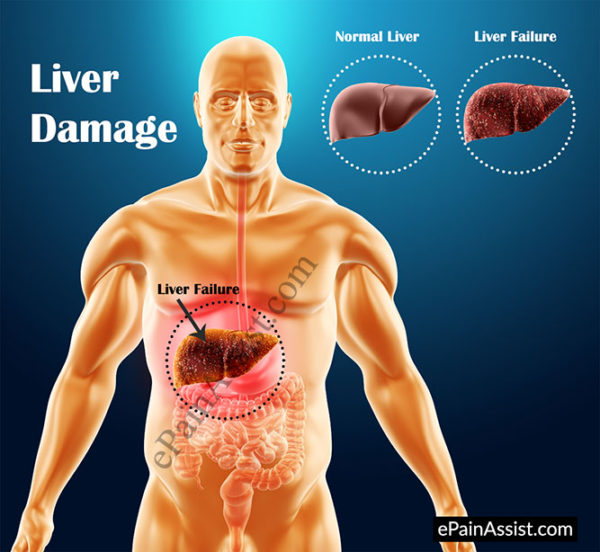

Stages of Liver Damage, Illustration – Stock Image – C027/6479 …

Illustration showing a healthy liver (left) and cirrhotic liver Stock …

Stages of liver damage. Starting from a healthy liver (top left Stock …

Normal Liver Versus Liver with Cirrhosis Stock Vector – Illustration of …